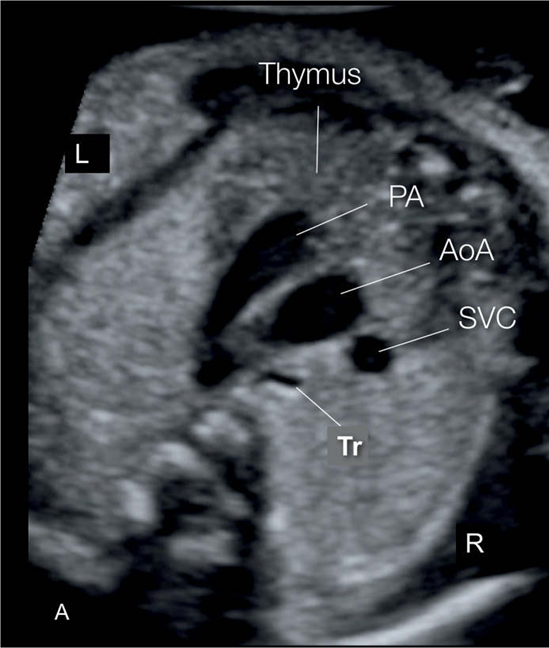

Identify structures of the heart